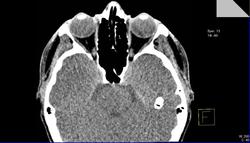

Под стрелками артефакт? или?

Вот-вот!Меня тоже ничего не смутило.Я и сделал заключение:норма.В направлении ничего толкового написано не было.А почти 2 недели спустя офтальмолог мне с пеной у рта доказывает,что у пациентки отёки необъяснимые в  последнее время,а я(такой-сякой) не вижу утолщения внутренней прямой мышцы глаза!

Я присмотрелся и согласился с ней,извинился,переделал протокол,а про себя поругал за невнимательность.Потом стал присматриваться при других исследованиях(глазниц,головного мозга) к глазницам и почти у всех внутренняя прямая мышца толще и плотнее остальных мышц.

Отсюда вопрос:есть тут или нет эндокринная офтальмопатия?

На сколько я знаю мышцы глаза не должны быть одинаковыми по толщине. На сайте есть замечательная лекция по патологии орбит.

Посмотрите вот здесь нормальные размеры мышц, а также как измерить положение глазных яблок, разница в положении не должна быть более 1 мм.

Мышцы лучше измерять на короналах.

Здесь ничего особенного не вижу. На мой взгляд норма.